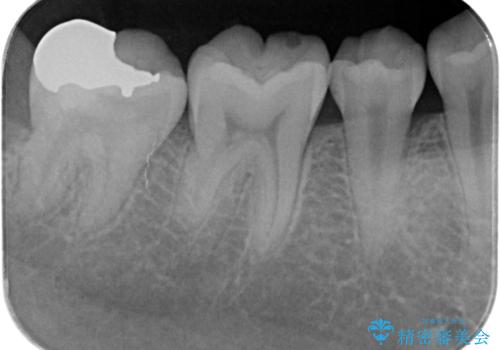

- 検査の結果虫歯が見つかった患者様です。

親知らずを抜歯してから虫歯を除去した後、ゴールドの詰め物で修復します。

比較的大きな虫歯でしたがゴールドでの修復にすることで歯の削る量を抑え、精度の高い治療を行うことができました。

親知らずの問題も同時に解決することで今後の虫歯リスクを抑えています。